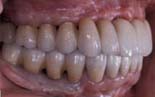

| 治療後、自然な形の歯がインプラントによって支えられています。 |

| 術前のレントゲンでは上顎の奥歯の部分には3mm程度の骨しかありませんでしたが、サイナスリフトを行なうことにより、治療後には15mmのインプラントが数本入りしっかり奥歯を支えています。 |

この方の治療後の全体像です。治療前と比較して、同じ方だと信じられますか?

この方の人生の質は大きく改善しました。